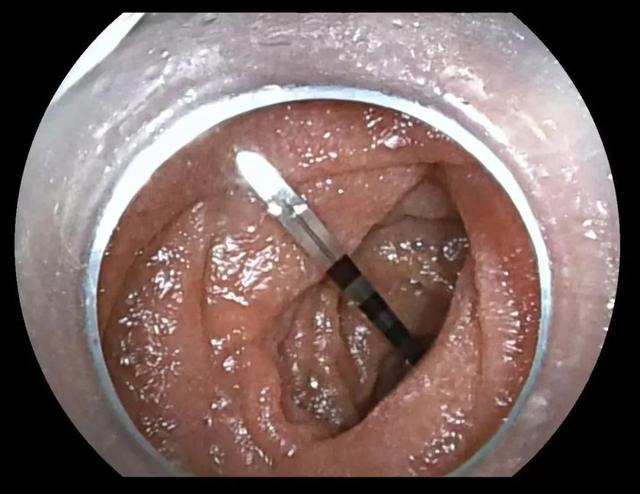

消化内科的医生当机立断,决定利用小肠镜经自然腔道(即消化道)取出异物。

医生将小肠镜经口插入小肠,用圈套器“轻挑慢剔”,夹出了这枚3厘米长、一端尖锐异常的钻头,且有效避免了对消化道黏膜的二次损伤。术后第二天,沈大爷就平安出院了。